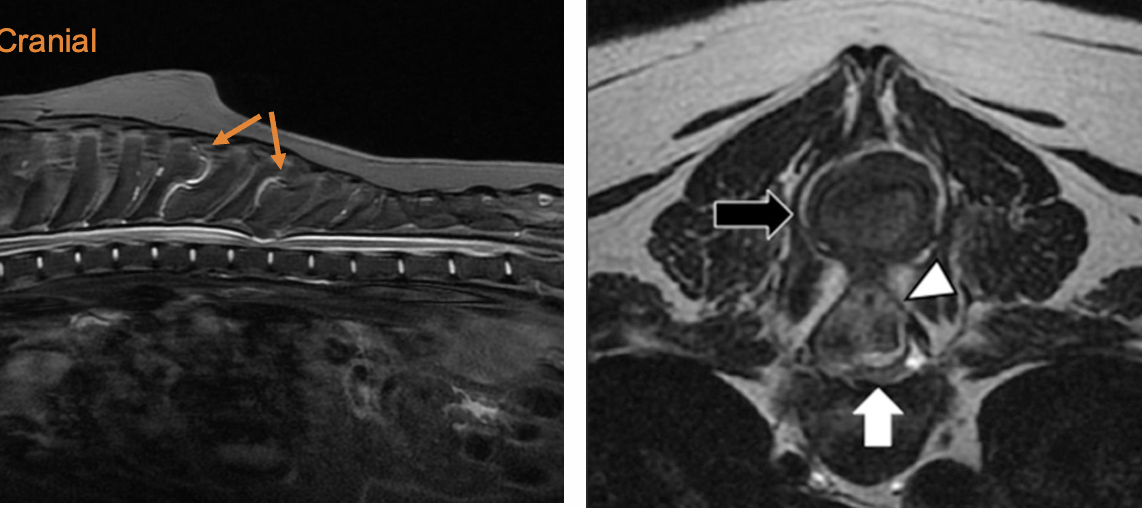

Q

A

multiple cartilaginous exostoses with a nodule pushing down onto the spinal cord